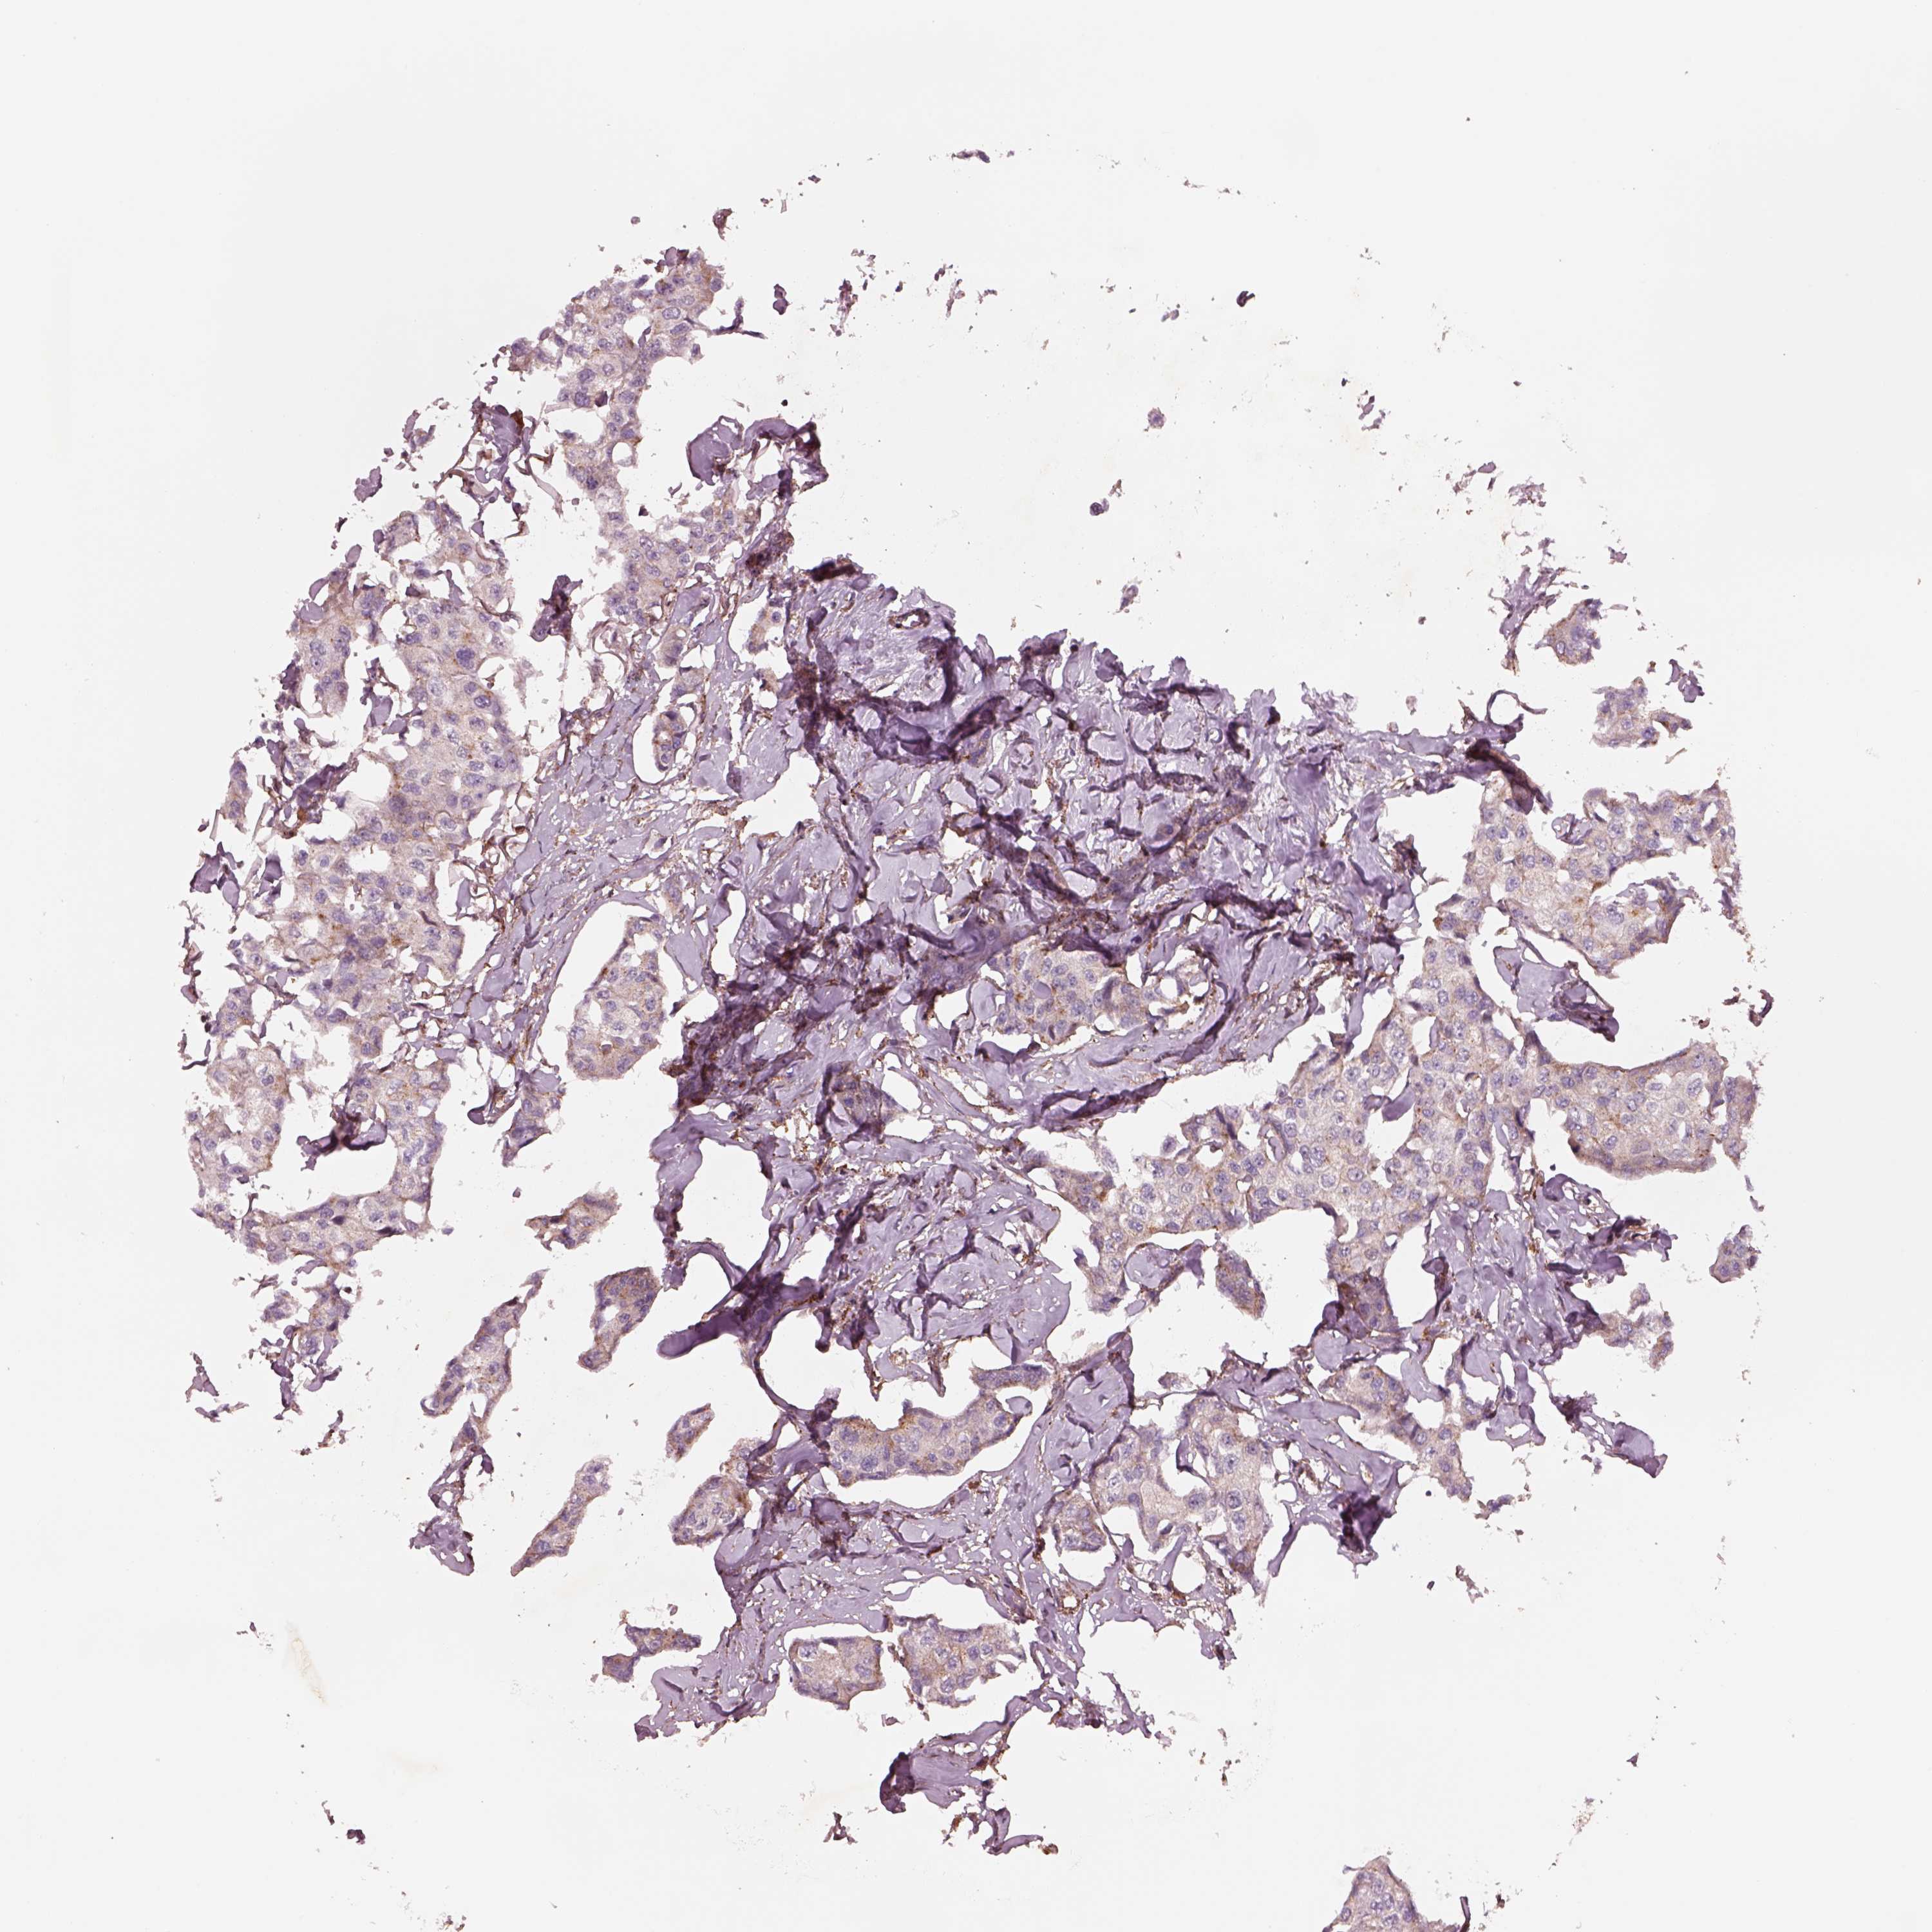

CANCER BREAST CANCER Show tissue menu

BRCA TCGA BRCA VALIDATION PROTEIN EXPRESSION